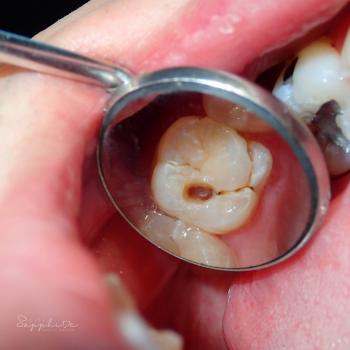

The image shows:

Side-to-side movement being tested.

Visible mobility between the premolar/molar region.

Gingival margin appears slightly inflamed → possible periodontal involvement.